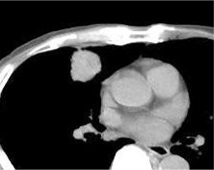

Degree of Enhancement of the lesion on DSA and arterial infusion CT

完全染色的病变(Total enhancement of the lesion)

部分染色的病变(Partial enhancement of the lesion)

Ring enhancement of the lesion